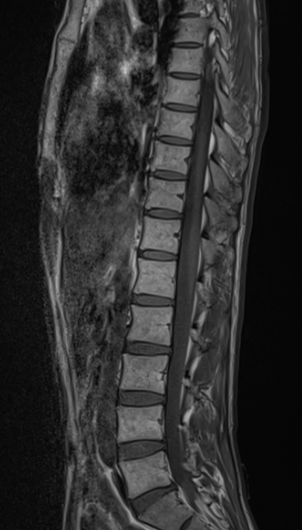

척추 mri를 찍어서 봤는데 저런식으로 홈이나 금간것저럼 보이는게 있는데 저건 뭔가요???

뼈에 금이 간게 아니라면 뭔지 궁금합니다

• 4번 째 사진

이런 경우에 골절이 아닌지 오해하시는 경우가 많은데 골절이 아닙니다.

골절의 경우에는 T1 영상에서 조영이 떨어지고 fat suppression T2 영상에서 조영이 증가하는 소견을 확인해야합니다.

골절이 아니면 왜 저렇게 보이는지 까지는 제가 잘 모르지만 저 소견을 이상소견으로 보이는 않습니다.